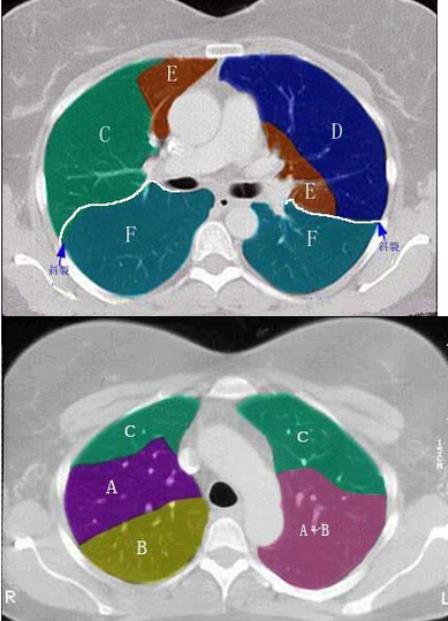

- 单项选择题 结合肺段模式图,选出右肺上叶的组成()。

- C